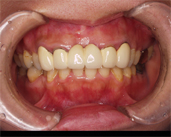

![]() |

(吉本歯科医院でのセラミックの治療をやりかえた完成写真 上の前歯2本) 歯茎との境目に違和感がなく、ご自分の歯のように見えます。治療していない両隣の歯の色、風合いに合わせて被せものをつけています。 |